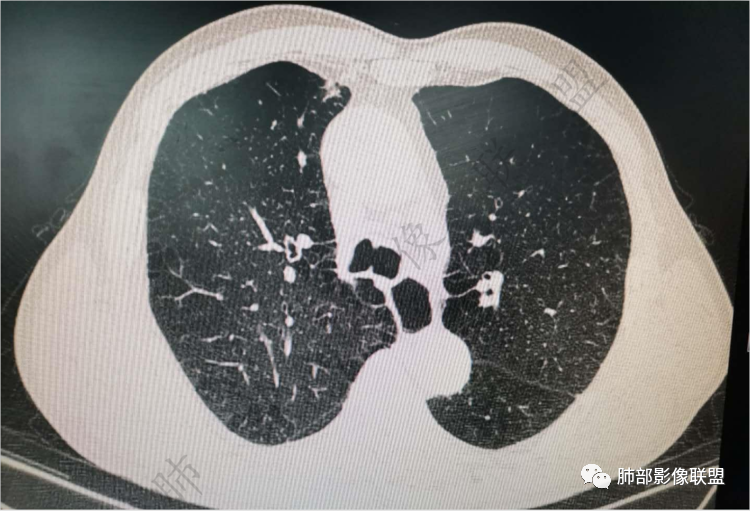

肺气肿背景

实性有隆起的小结节,内部有坏死、周围包括内乳动脉有增粗

右上叶前段结节,肺气肿背景,血管滋养丶支气管截断,与纵隔脂肪间隙清析

老年男性,肺气肿背景,右肺上叶前段胸膜下结节,部分边缘毛糙,血管集束增粗,支气管似有截断,胸膜牵拉,结节密度不均,两个月随访结节有增大,考虑恶性,肺癌可能;另右肺上叶后段肋胸膜区小片状类结节影,考虑炎性可能。

支气管变形、壁增厚,提示慢性支气管炎症

边缘平直

宽基底与胸膜相连,附近胸膜增厚,糊墙

内乳动脉关系似乎不密切

内部有低强化区,边界尚清

还是支持炎性放前面,恶性待排